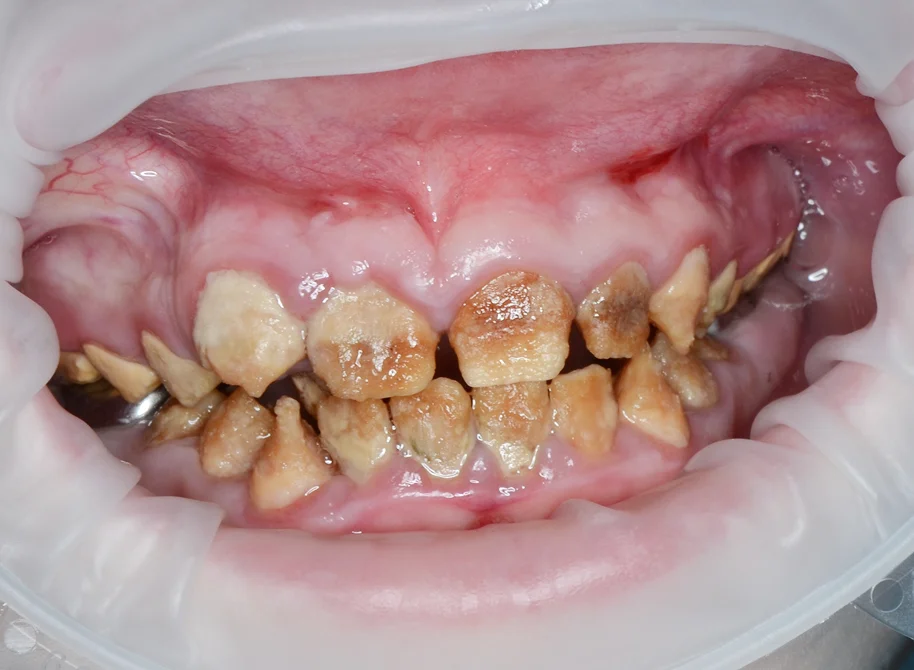

Олигодентия, адентия, сверхкомплектные зубы: диагностика и план лечения.

Основные состояния, сопровождающиеся нарушением числа зубов. Наиболее частые локализации сверхкомплектных зубов. Последствия олигодентии и сверхкомплектных зубов.

Аномалии формы: от шиловидного резца до секторальной одонтоклазии.

Микродентия, макродентия, синодонтия, геминация — диагностика и тактика лечения. Сочетанные случаи. Показания к подростковому протезированию при микродентии.

Пороки твёрдых тканей: дифференциальная диагностика

Молярно-резцовая гипоминерализация (MIH), флюороз, несовершенный амелогенез, дисплазии дентина — клинические признаки каждого состояния и границы между ними. Классификация Wuerzburg 2.0. Дисплазии дентина: от облитерации пульповой камеры до «зубов-призраков».